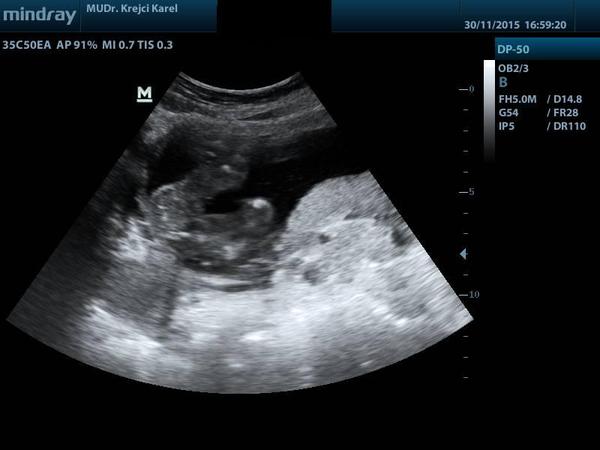

Je na ultrazvuku holčička?

při zvětšení vidím stydké pysky ..vidím dobře? 😉

Přesně tohle jsem taky viděla na utz. Je to holka ☺

Taky bych to videla na holcicku. U obou synu jsem v tomhle tydnu na UTZ videla jasneho pindika.